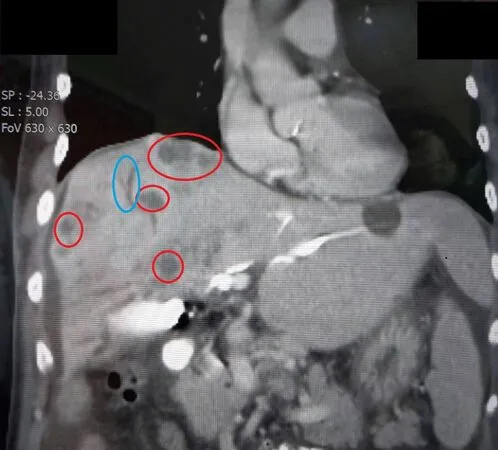

▲病人經檢查發現,肝臟布滿腫瘤(紅圈)、肝內膽管異常擴張(藍圈)。(圖/大千醫院)

66歲張姓男子近半年內體重無故減輕4公斤、食慾減退、精神不濟,近日更出現皮膚與眼白發黃、皮膚搔癢及深色尿液等症狀,急赴醫院求診。經檢查發現其肝臟布滿腫瘤、肝功能及膽紅素(黃疸指數)異常升高,最終確診為晚期膽管癌,已出現肺部轉移跡象。